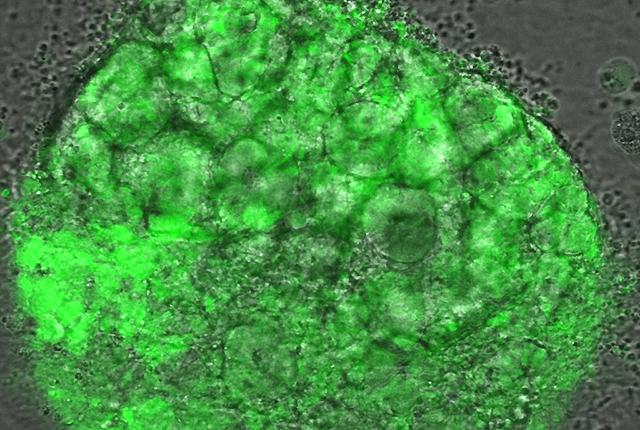

A. Yes, because you have a little piece of human kidney structure. It looks and functions similar to kidney tissue at a rudimentary level. We can perform careful experiments to see exactly what's happening; you can watch these kidney cells under the microscope and begin to understand what is occurring in the context of COVID-19. We are using organoids as a surrogate for people.

A. One thing we found is that the organoids can be infected; infectious virus can get into cells in kidney organoid cultures and is capable of replicating under those conditions. Others have begun to report this in literature as well. And we can shed some light on which types of kidney cells appear most susceptible to COVID-19.